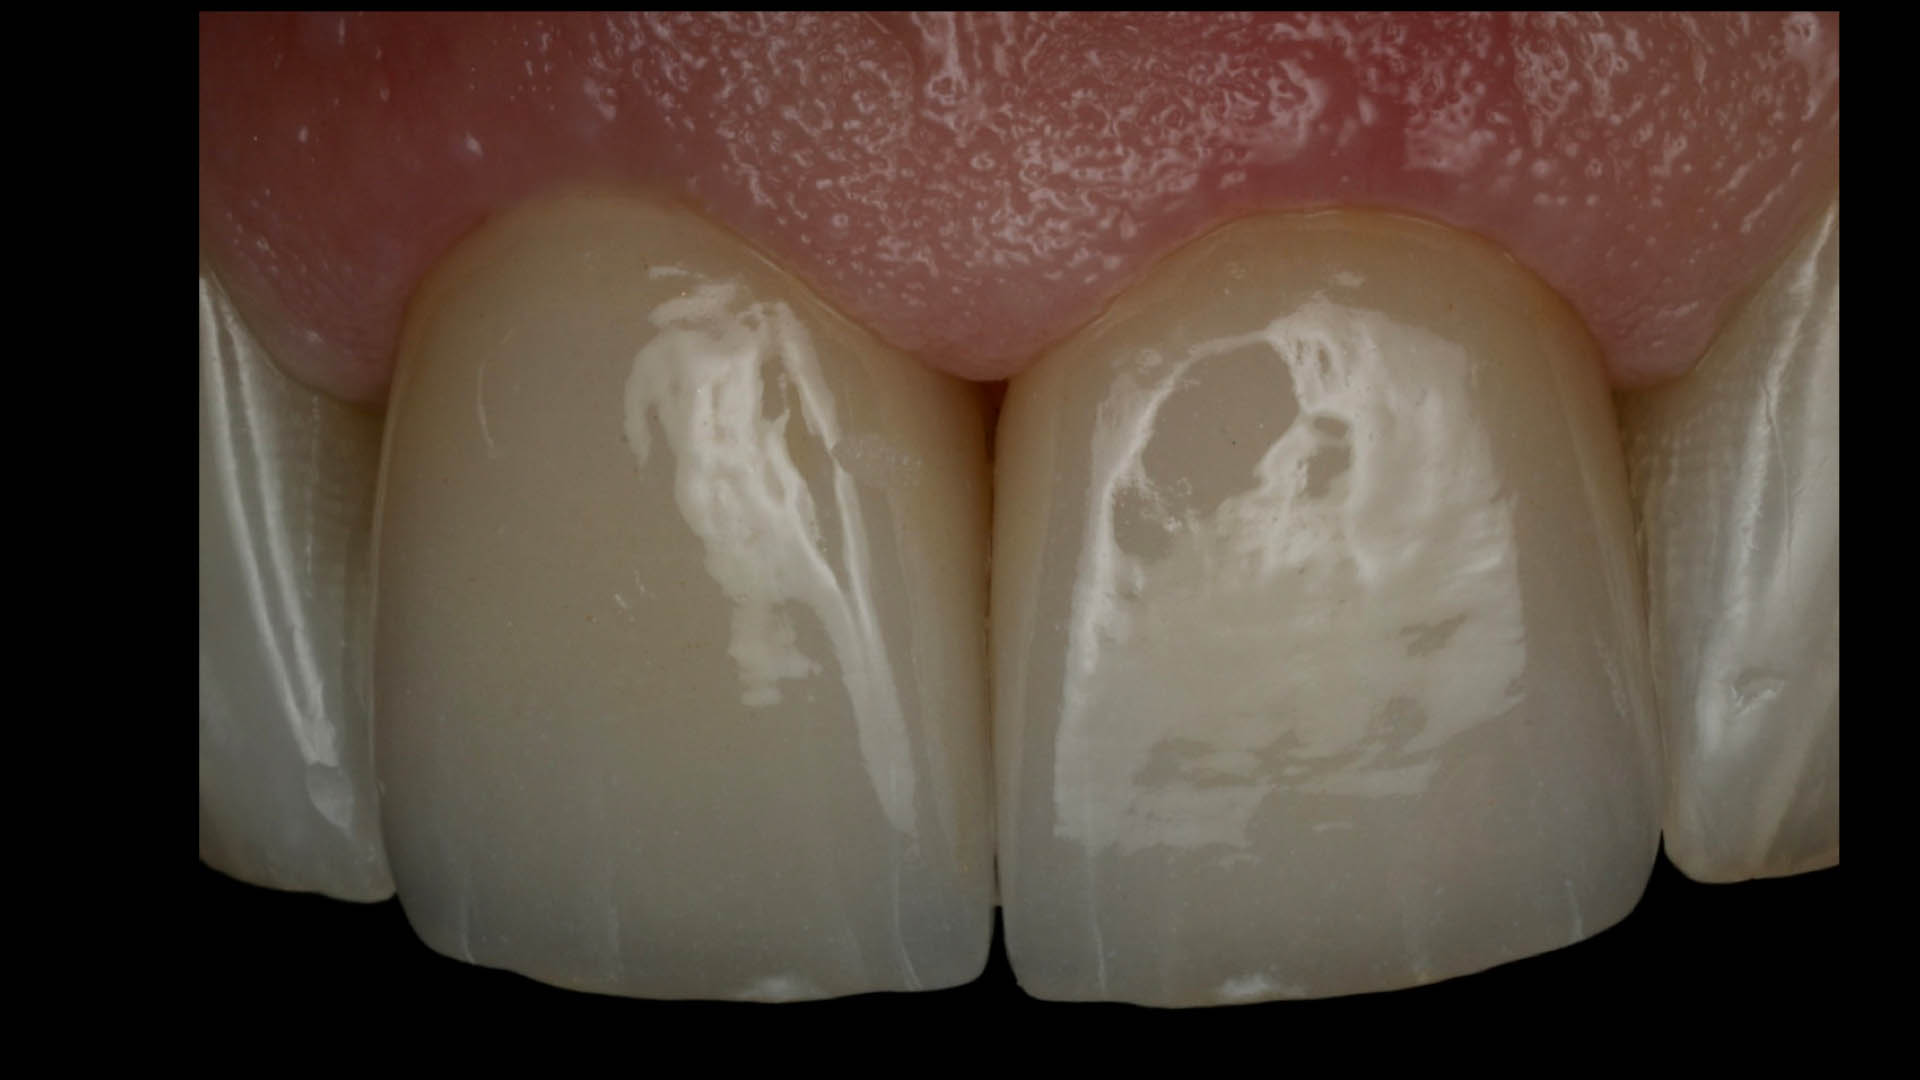

Take a glimpse into the magic of Coral Gables Dentistry through our before and after pictures. See firsthand the incredible smile makeover transformations that have brought confidence and joy to our patients.